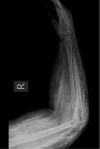

Methods: Two cases were compared in the context of the prevailing literature. One of these was a large volume extravasation of an iodine-based imaging contrast agent with a diffuse distribution pattern, rendering it unsuitable for this method of evacuation. This is contrasted with a case with a more discrete collection better suited to acute evacuation.